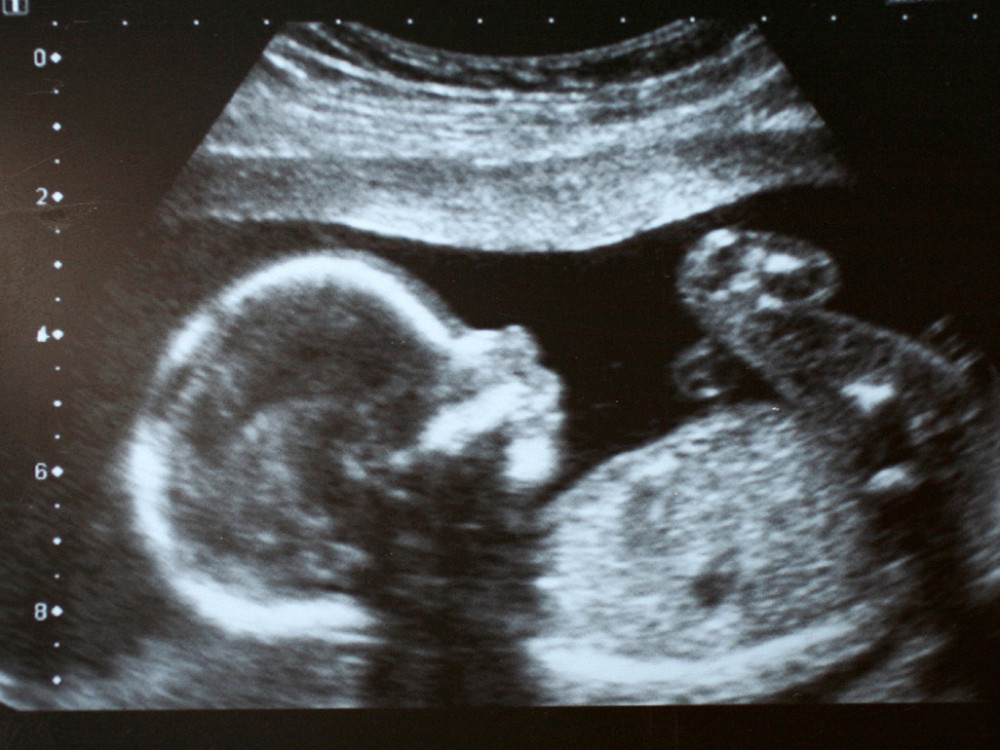

Ovako izgleda beba koja štuca u materici (VIDEO)

Mia Borisavljević ne krije da jedva čeka susret sa naslednicom, a fotografrafija ultrazvuka otkrila prelepu stvar! (FOTO/VIDEO)